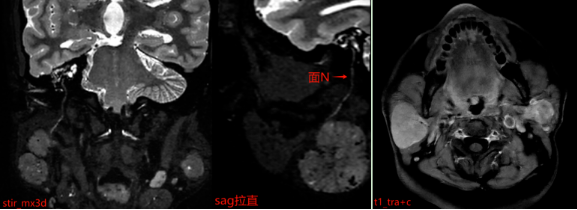

患者接受了磁共振(MR)检查,影像表现如下:

MR表现:双侧腮腺浅叶下极见结节状略混杂信号,T1以低信号为主、T2以 稍高信号为主,DWI呈稍高信号,ADC图呈稍低信号,边界清晰,增强扫描病变中等强化,强化较均匀,其内见点状无强化影。

报告中特别提到“加扫stir_mx3d序列”,这一步骤非常重要。该序列能更清晰地显示病变与周围神经、血管的解剖关系。腮腺区域内走行着重要的面神经,它控制着我们的面部表情肌肉。如果手术中损伤该神经,可能导致术后面瘫,影响患者闭眼、微笑等基本功能。